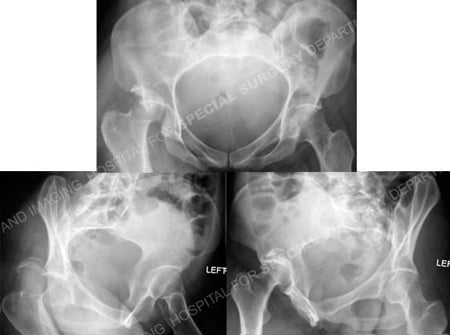

Anteroposterior and Judet radiographic views (Obturator Oblique and Iliac Oblique views) revealing

a right-sided Posterior Wall acetabular fracture and associated posterior hip dislocation.